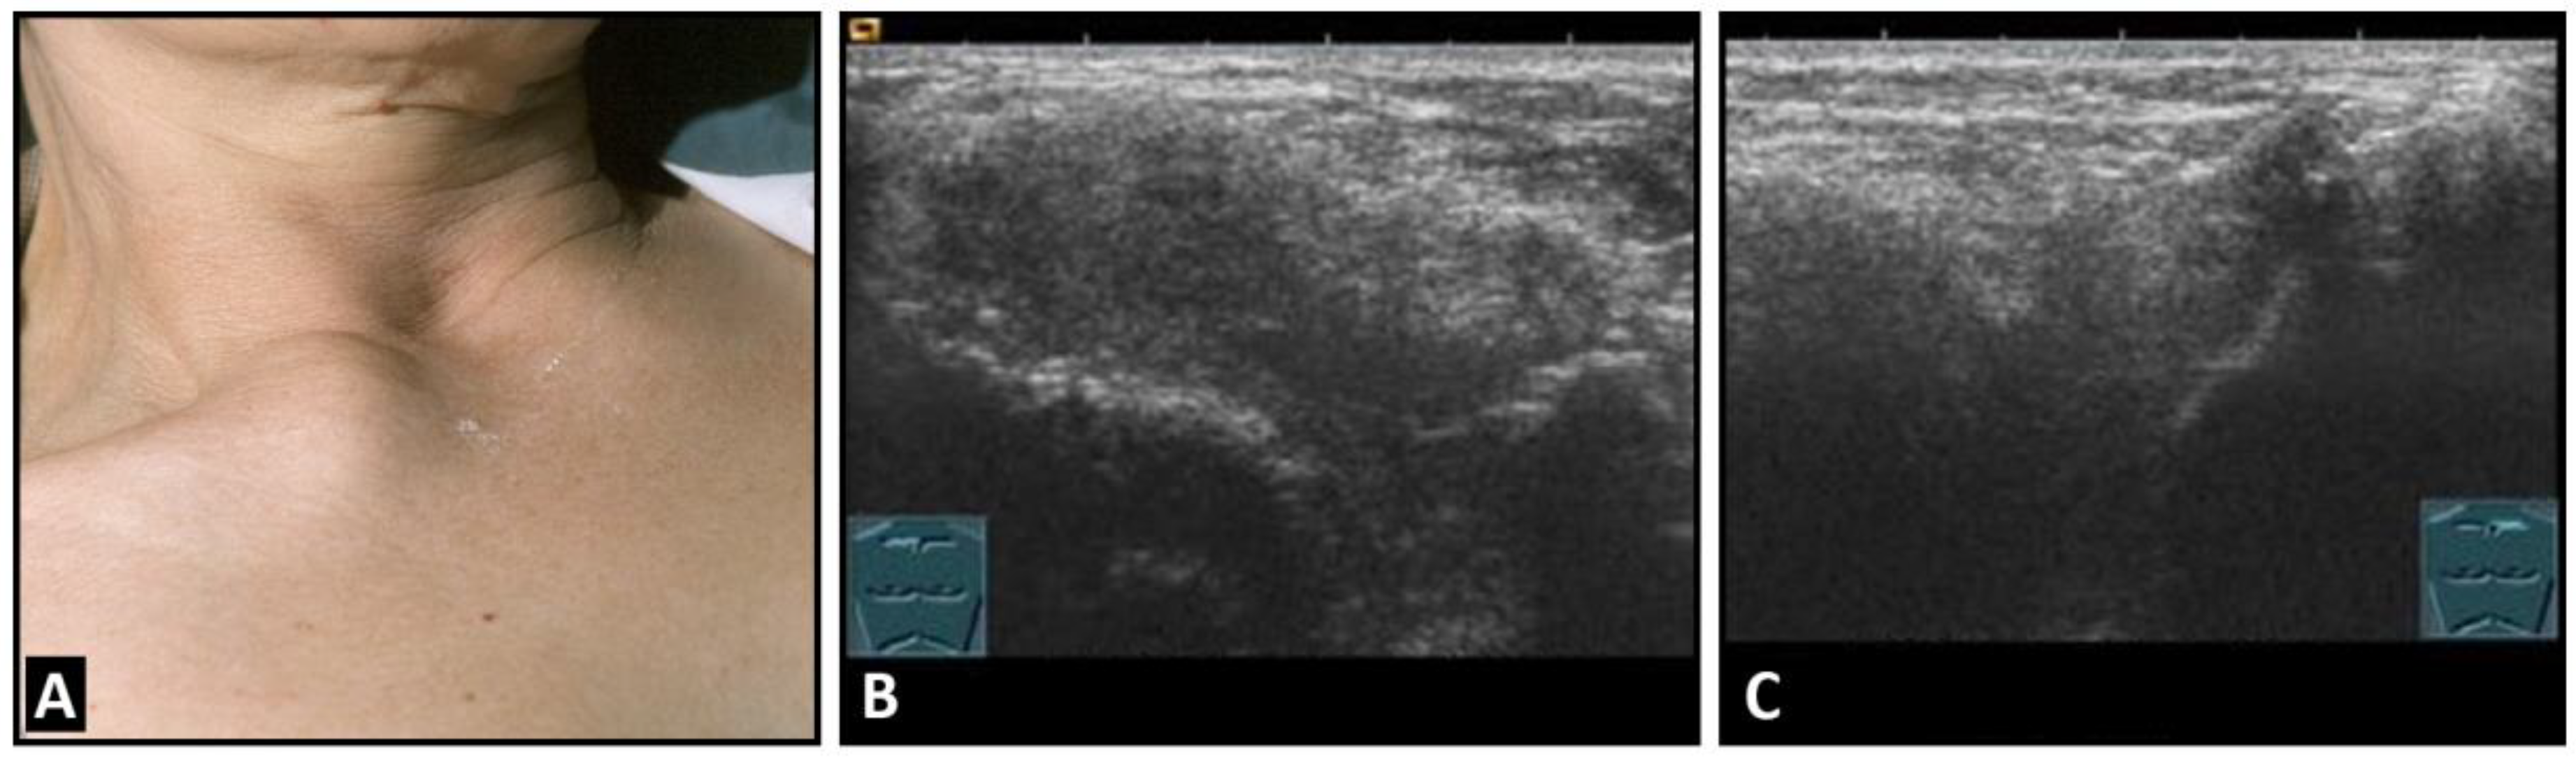

Figure 6.

A patient with painful swelling of the right sternoclavicular joint (A). B-mode US shows a hypoechoic swelling similar to that in Tietze syndrome (B) in comparison with the contralateral left joint (C).